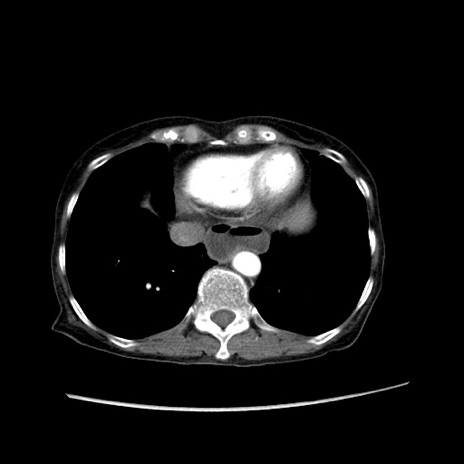

症例25(横断像)

【症例】80歳代女性

【主訴】胸のつかえ感

【現病歴】約9時間前に食後から胸のつかえた感じあり、嘔吐あり、来院。

【既往歴】胃癌(全摘)、胆摘、虫垂炎

【身体所見】心窩部に圧痛あり、反跳痛なし。

【データ】WBC 5700、CRP 0.05